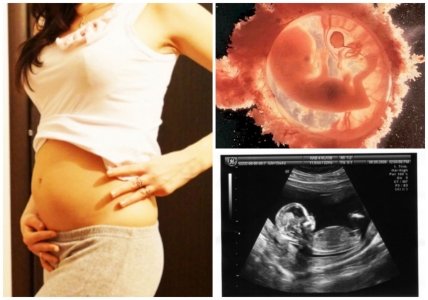

В конце 13 недели будущий малыш весит около 20-30 г., его рост 9-10 см., а диаметр головы приблизительно 2,5-3 см.

Большую часть времени кроха плавает в амниотических водах во сне, однако, когда он бодрствует, то с помощью УЗИ можно заметить, как его ручки сжимаются в кулачки, от сосет пальчик или вздрагивает.

У него активно формируется костная система: удлиняются кости рук и ног, образовываются первые ребра, идет процесс окостенения позвоночника и черепа. К этому сроку у малыша заложены уже все молочные зубы, на пальчиках появились отпечатки, поджелудочная железа вырабатывает первый инсулин.

Голова будущего малыша уже не прижата к груди, на лице можно четко различить черты лица, подбородок, переносицу, по бокам головы расположены ушки, уже почти на своих местах глаза, однако, они еще закрыты плотно сросшимися веками.

Щитовидная железа крохи уже достаточно развита, а дыхательная система– хорошо сформирована. Ребенок дышит, тренируя мышцы диафрагмы и грудной клетки, его голосовая щель пока плотно закрыта. Происходит и половая дифференциация: у мальчика начинает развиваться предстательная железа, а генитальный бугорок удлиняется в пенис, у девочки расположенные в брюшной полости яичники опускаются в область таза, а генитальный бугорок загибается вниз – из него сформируется клитор.

Кожный покров крохи пока еще очень нежный и тонкий, кожа красная и морщинистая, на ее поверхности проступают мелкие кровеносные сосуды. Это объясняется тем, что пока у малыша отсутствует слой подкожной жировой клетчатки.